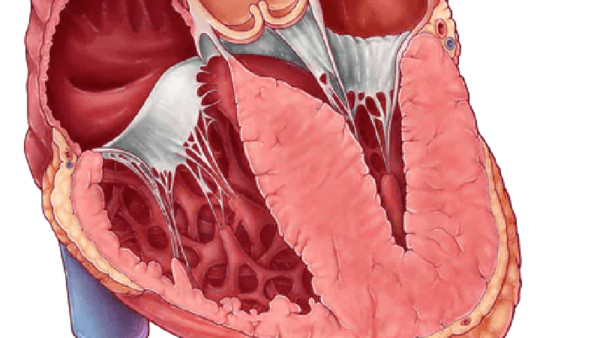

La miocardiopatía hipertrófica se caracteriza por la hipertrofia del ventrículo izquierdo, la cual no está relacionada con condiciones de sobrecarga de presión o volumen, como sería el caso en situaciones de hipertensión arterial o enfermedades valvulares. Esta definición ha experimentado una evolución significativa a lo largo del tiempo. Anteriormente, la HCM se definía predominantemente por la presencia de una obstrucción al flujo de salida del ventrículo izquierdo, que se producía como resultado de la hipertrofia del septo interventricular. Sin embargo, las definiciones actuales amplían este concepto para incluir cualquier caso en el que el grosor de la pared del ventrículo izquierdo supere 1.5 centímetros, tal como se mide mediante ecocardiografía. Esta ampliación permite identificar formas de HCM que no generan obstrucción del flujo de salida, lo que es crucial para el diagnóstico y manejo adecuado de la enfermedad.

La distribución de la hipertrofia en el ventrículo izquierdo también puede variar. En muchos casos, el septo interventricular puede presentar una hipertrofia desproporcionada, lo que se denomina hipertrofia septal asimétrica. No obstante, existen casos donde la hipertrofia se localiza en otras áreas del ventrículo, como en la mitad del mismo o incluso en el ápice. Esta heterogeneidad en la presentación de la enfermedad subraya la necesidad de un enfoque personalizado en el diagnóstico y tratamiento de los pacientes con HCM.

En un corazón normal, la anatomía del ventrículo izquierdo permite que el ápice tenga un grosor relativamente delgado. Sin embargo, en el contexto de la miocardiopatía hipertrófica, se pueden desarrollar complicaciones significativas que afectan esta región. Durante la sístole, la obstrucción del flujo de salida en el ventrículo izquierdo puede provocar un fenómeno donde la sangre se acumula justo por encima del ápice, generando presiones intraventriculares extremadamente elevadas. Esta situación puede dar lugar a la formación de un aneurisma en el ápice, una dilatación anormal que puede comprometer aún más la función cardíaca.

El tracto de salida del ventrículo izquierdo tiende a estrecharse durante la sístole como resultado de la hipertrofia del septo interventricular. Este estrechamiento se ve acompañado de un movimiento anterior de la válvula mitral. La válvula mitral anterior es arrastrada hacia el flujo de salida, lo que puede aumentar la obstrucción en el tracto de salida y contribuir a un ciclo de disfunción hemodinámica.

Por otra parte, es común que el ventrículo izquierdo esté más afectado que el ventrículo derecho en esta enfermedad, y como consecuencia de las presiones elevadas y la alteración del flujo sanguíneo, las aurículas, especialmente la aurícula izquierda, suelen experimentar un agrandamiento significativo. Este agrandamiento es indicativo de la sobrecarga de volumen y presión que experimentan estas cavidades en respuesta a la disfunción del ventrículo izquierdo. La atención a estos cambios estructurales y funcionales es esencial para el diagnóstico y manejo adecuado de los pacientes con miocardiopatía hipertrófica, subrayando la complejidad de esta condición y la necesidad de un enfoque multidisciplinario en su tratamiento.